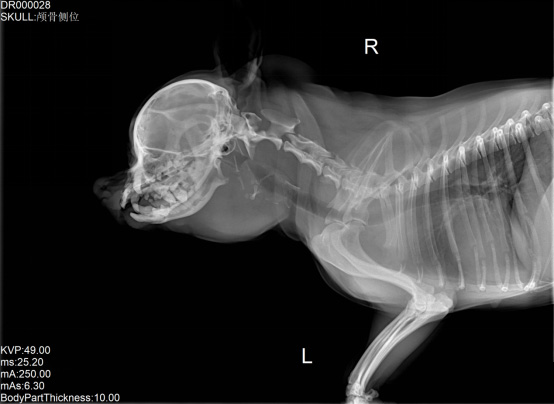

宠物DR是专业用于宠物X光拍摄的数字化X射线检查,辅助宠物医生进行及时精确的诊疗。宠物DR主要包括五大主要部件,数字X光探测器,高压发生器,球管,机架,宠物专用的DR工作站软件。宠物DR由于采用数字技术,自动成像处理,模拟X线图像向数字化X线图像的转变。宠物DR与传统模拟X光机相比有什么优势呢?采集时间10毫秒以下,成像时间仅为3秒,较高的空间分辨力和低噪声率,提高了病灶的检出率,避免漏诊误诊等问题。减少X线对人体照射的不良影响宠物DR照片是您最佳的选择。提高宠物医生工作效率,总而言之,选择宠物DR是宠物医院的最佳选择。宠物医学影像学实现全数字化和无胶片化升级发展提高技术水平。